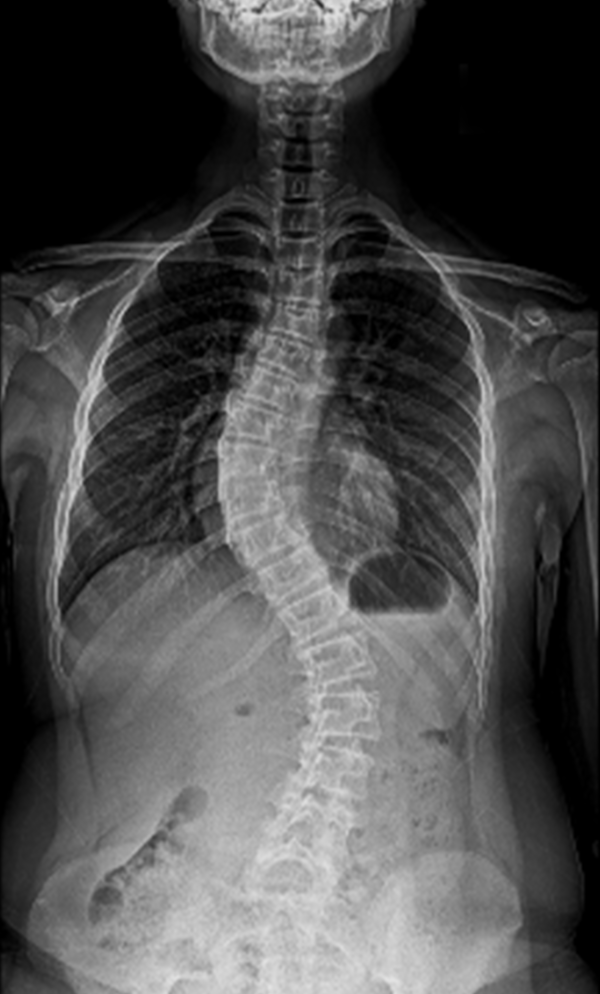

BEYOND RECOVERY : REAL STORIES

Gallery : Before - After